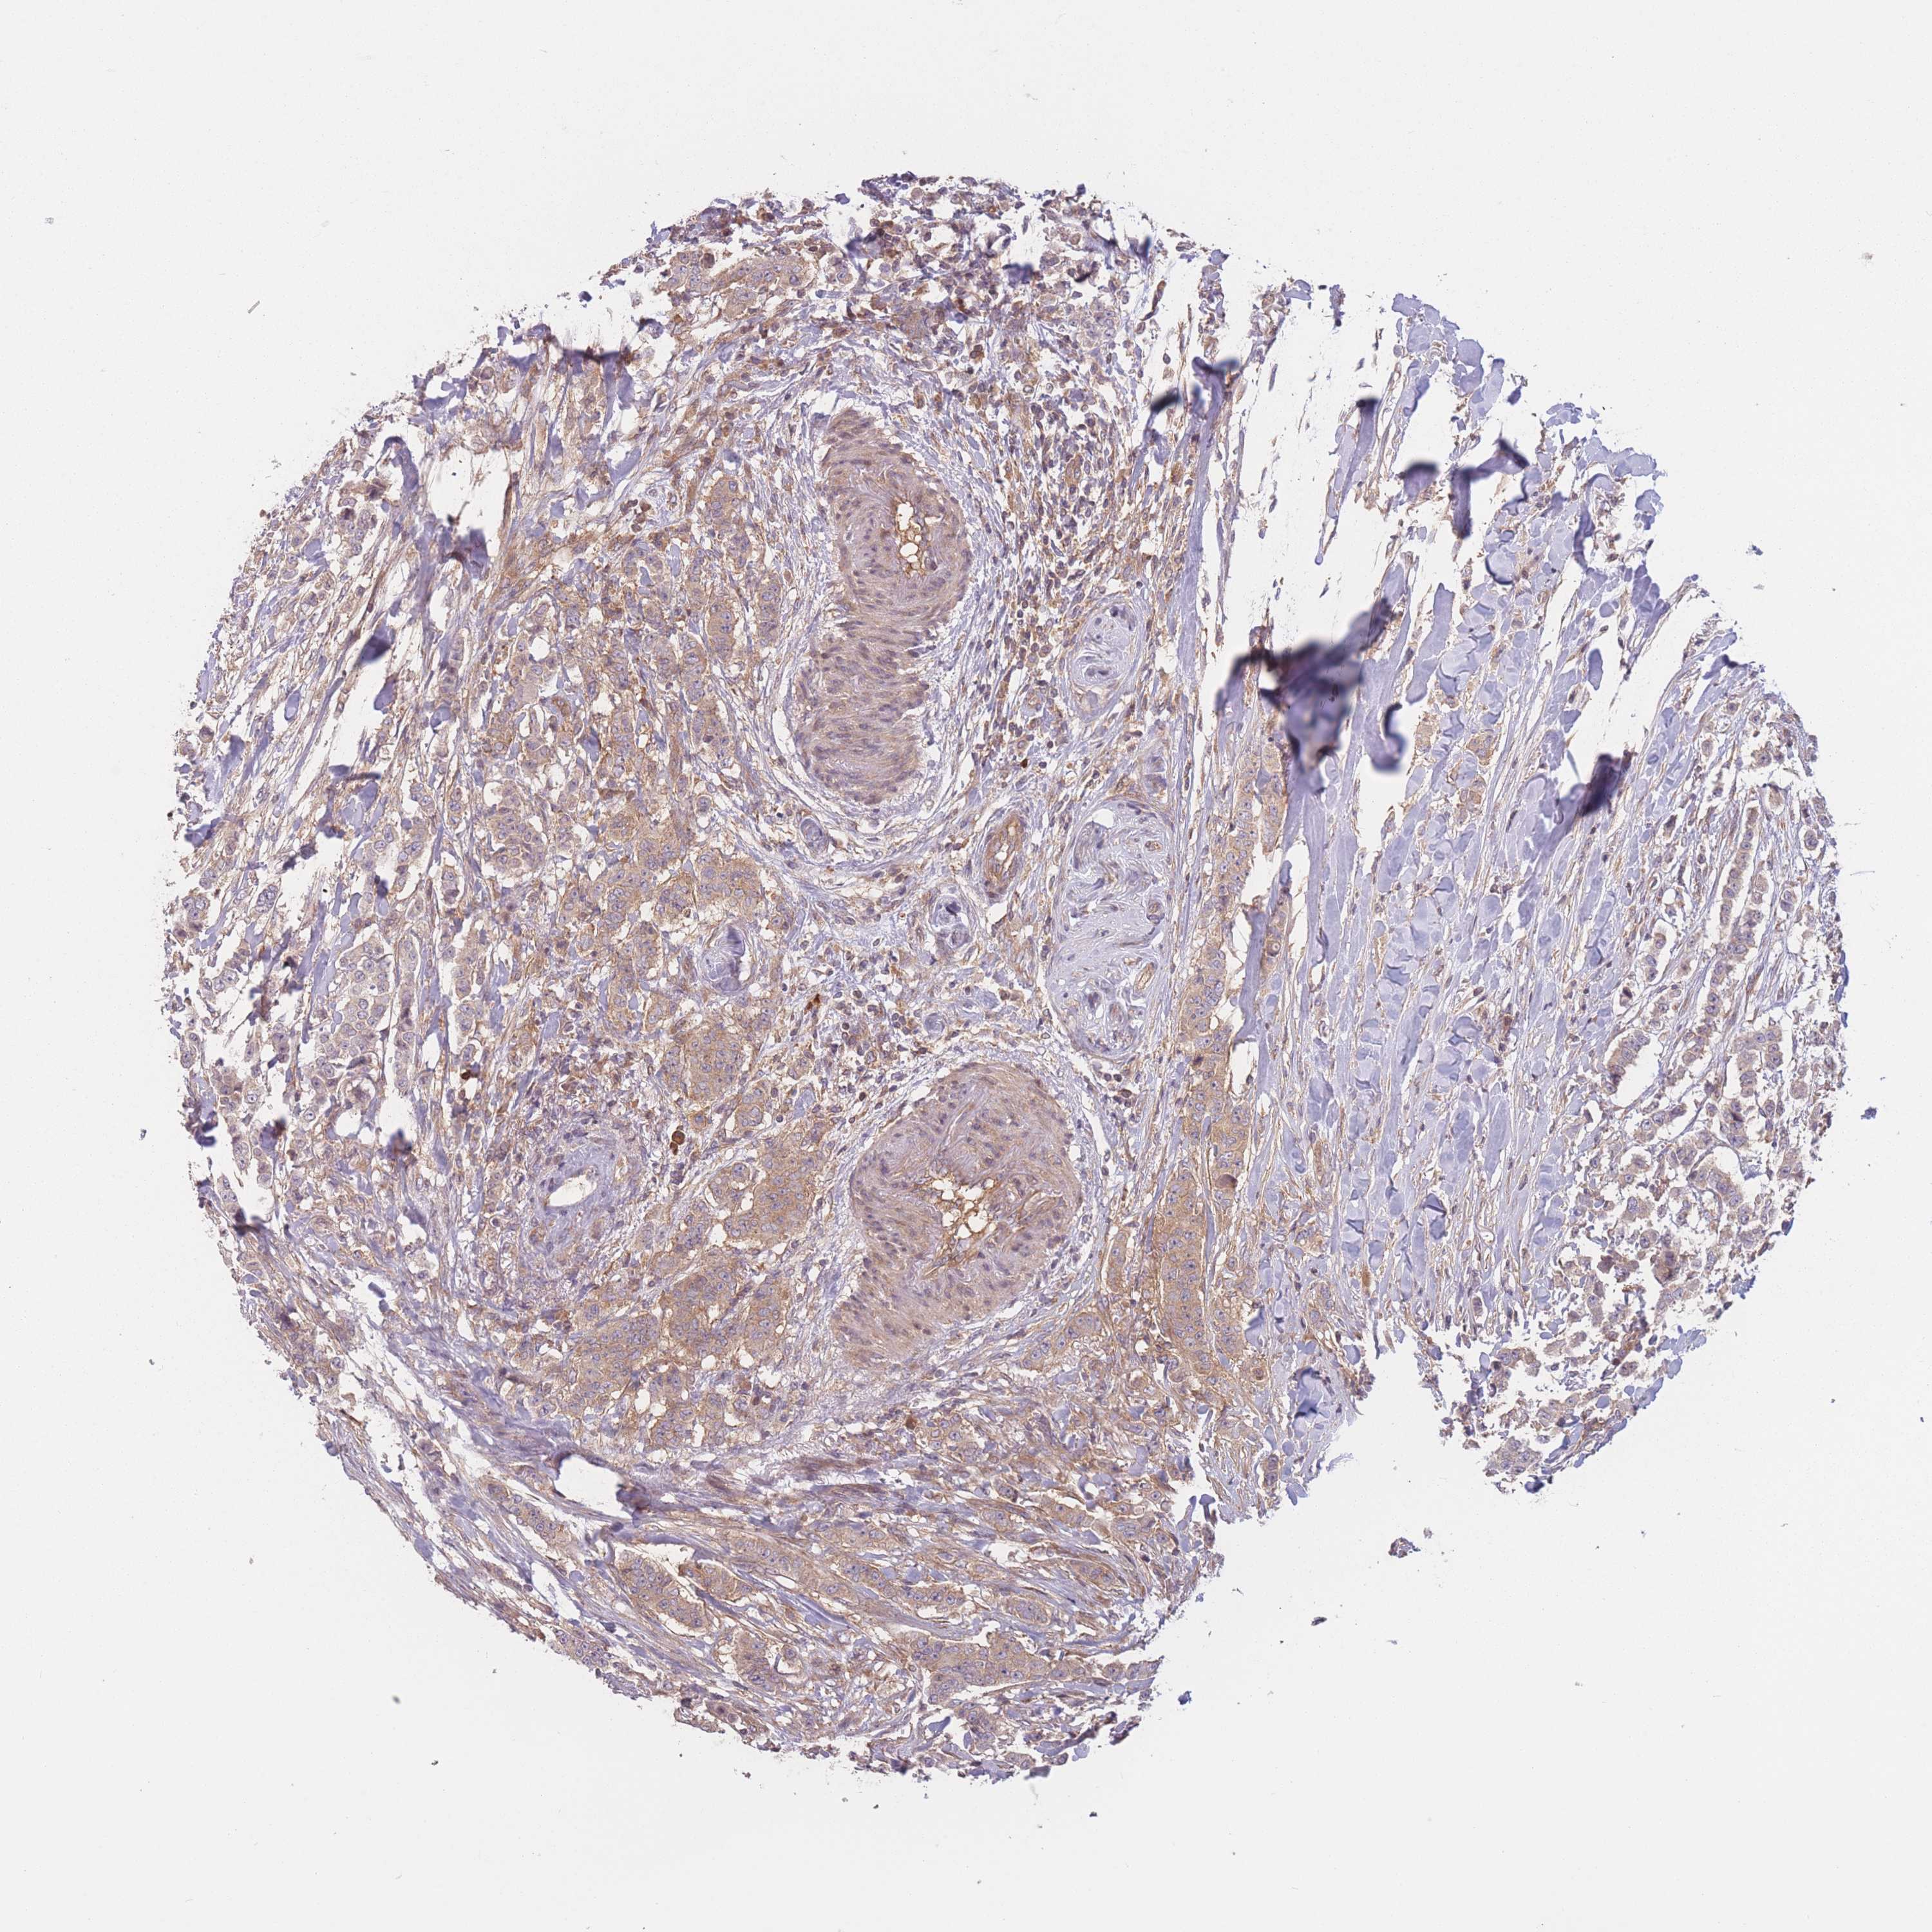

CANCER BREAST CANCER Show tissue menu

BRCA TCGA BRCA VALIDATION PROTEIN EXPRESSION